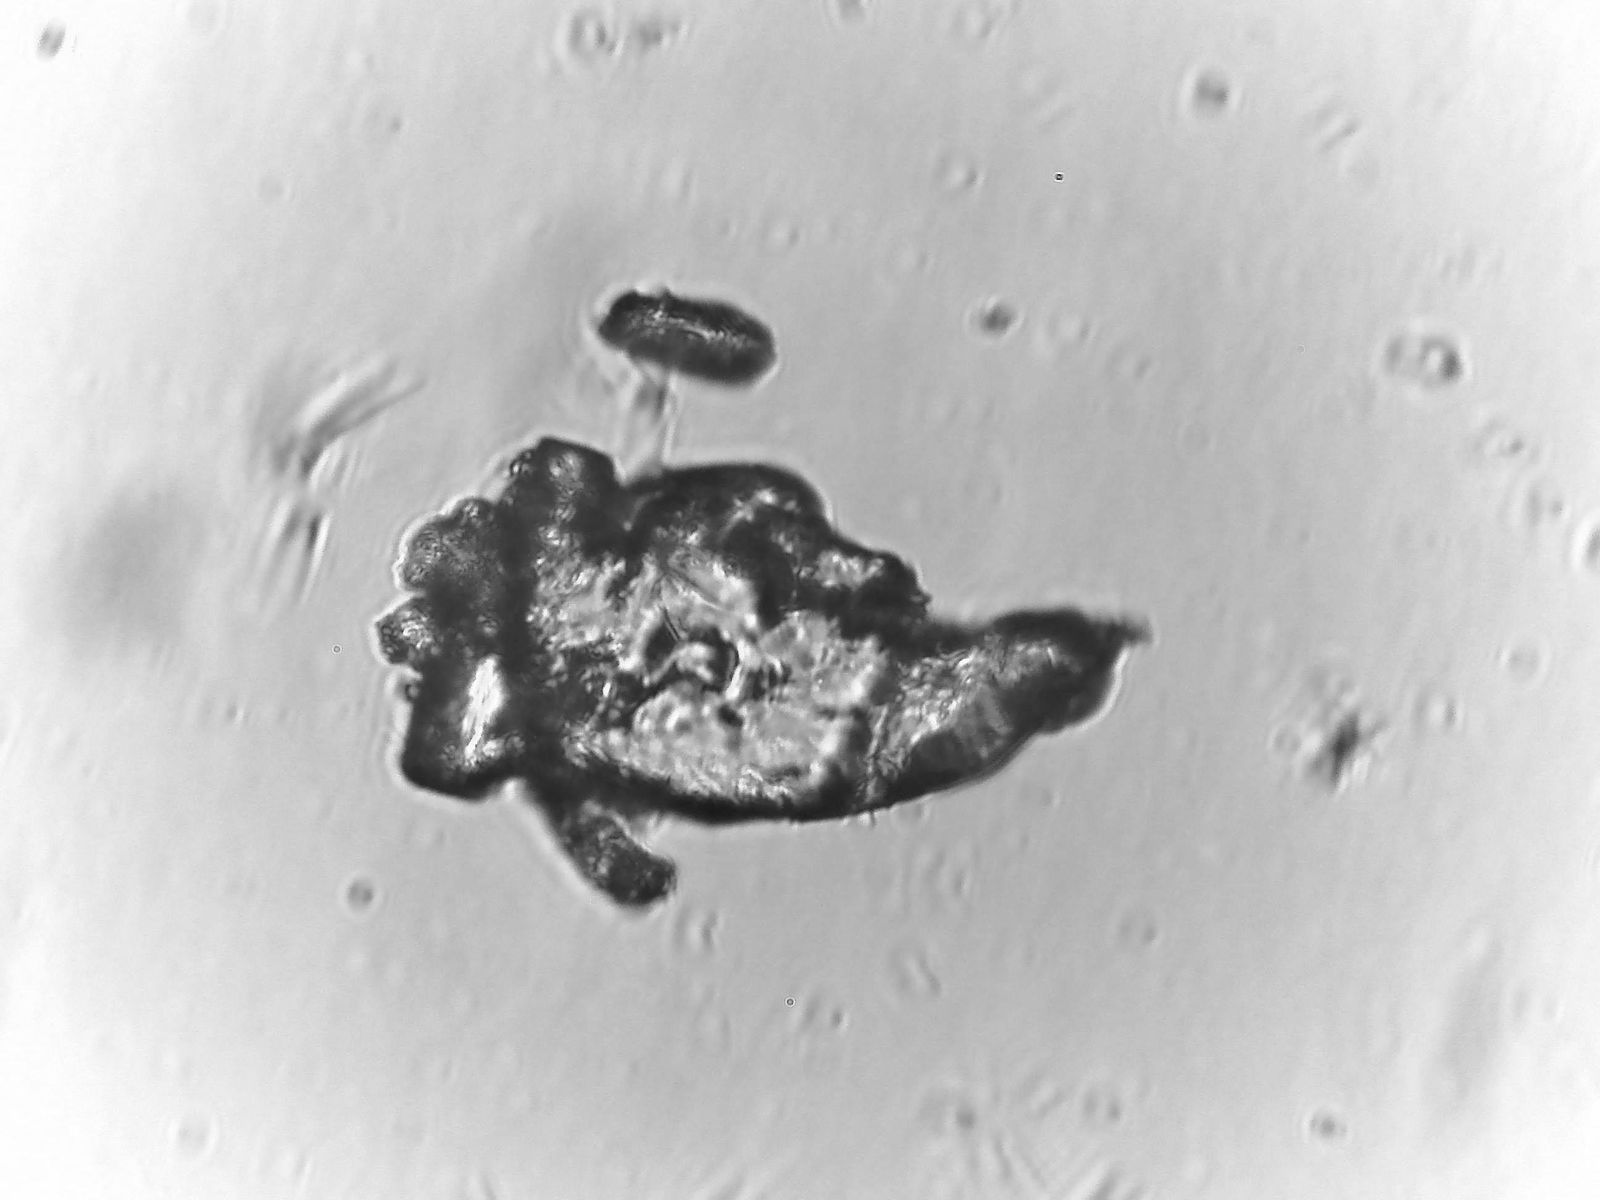

Das Ergebnis war erschreckend.

Ich habe Ihnen einige Bilder davon in den Anhang gelegt, was wir selbst "entdeckt" haben (kein Photoshop oder Fake!!)

Wir haben die Objektträger dann drei Tage liegen gelassen und wieder unter dem Mikroskop angesehen und mussten feststellen, dass sich neue Strukturen gebildet haben und die "alten" sich verändert haben.